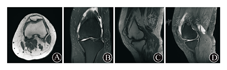

住院期间完善患者WOMAC问卷、KSS膝关节评分、Lysholm膝关节评分、SF-36生活质量评分(表1),同时完善各项术前检查。实验室检查未见明显异常,排除自身免疫性疾病或代谢障碍性疾病导致的关节炎。2018年9月17日(不均匀沉降术后17个月)于本院行站立位双下肢全长位片(图2 B),提示:"双侧膝关节骨质边缘骨质增生影,胫骨髁间棘增生变尖、肥大,双膝关节内侧关节间隙变窄,左侧为甚。左侧腓骨上段局部骨质缺损。余所示诸骨未见特殊"。图2中不均匀沉降术后15个月、17个月截骨高度7.5 cm,截骨长度2.4 cm,其他数据测量见表2。术前完善左膝关节MRI(图3),提示:左膝周围诸骨位置关系正常,股骨、胫骨、髌骨边缘增生变尖,膝关节及髌骨关节间隙变窄,关节面毛糙,关节面下见小斑片状骨质吸收灶及骨质水肿,左膝内外侧半月板前后角内信号欠均匀,可见小片状稍高信号影,内侧半月板及外侧半月板前角内异常信号延伸达关节面,前交叉韧带肿胀,股四头肌肌腱及髌韧带局部稍肿,后交叉韧带及双侧副韧带形态信号尚如常,关节腔及髌上囊内见少-中等量长T1长T2信号积液影,关节滑膜增厚。左膝周围软组织肿胀,髌下脂肪垫局部明显肿胀。MRI诊断结论:左膝退变:骨质增生;关节面下散在骨质吸收及骨质水肿;半月板变性,内侧半月板及外侧半月板前角撕裂;前交叉韧带肿胀,股四头肌肌腱及髌韧带局部稍肿;关节腔及髌上囊内少-中等量积液,关节滑膜增厚;左膝周围软组织肿胀,髌下脂肪垫局部明显肿胀。见腘窝囊肿。